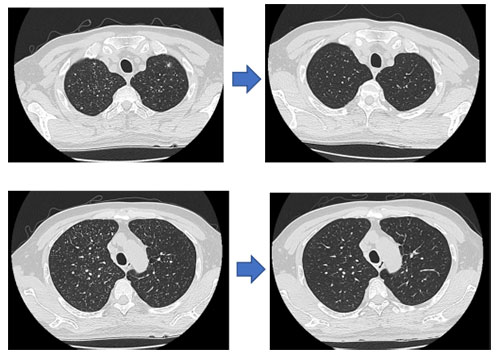

治疗前后患者胸部CT,经过治疗后,双肺多发粟粒样结节数量和面积均有明显减少。

挺好之一是小主人公小伍的“病情挺好”:从病死率极高的颅内结核中程度最重的病重状态终于一步步恢复到脑脊液指标好转,双肺多发粟粒样结节数量和面积明显减少,不再使用激素。